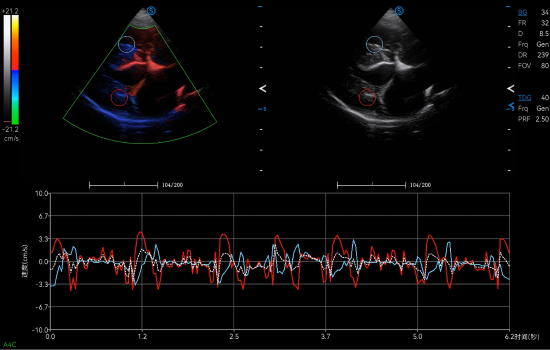

Cardiology Applications

● TDI QA automatically tracks and visualizes the strain and velocity of myocardial motion to facilitate comprehensive quantitative analysis for myocardial function evaluation

● AMM allows simultaneous assessment of cardiac wall motion for multiple sections, thereby facilitating efficient diagnosis of dilated cardiomyopathy for large-sized canines.

● CW Mode sensitively detects high-velocity blood flow signals to identify cardiac abnormalities such as mitral regurgitation, which is commonly observed in dogs with degenerative mitral valve disease.